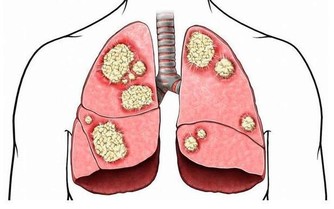

在新型肺炎的高危時期,禽流感又​​捲土重來了,讓大家的惶恐又加重了許多!

總是擔心自己萬一發燒、咳嗽、感冒……該怎麼辦?

實際上,大家除了少出門,勤洗手,多通風,出門戴口罩之外,提高自己身體的免疫力也是抵禦病毒的有效方法之一。